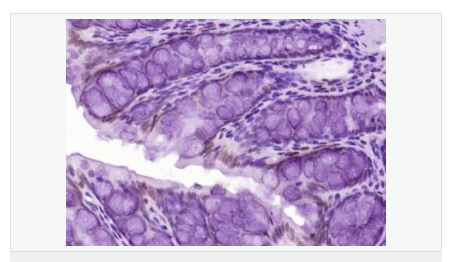

細(xì)胞定位細(xì)胞核 細(xì)胞漿

產(chǎn)品介紹The protein encoded by this gene is a member of the MAP kinase family. MAP kinases act as an integration point for multiple biochemical signals, and are involved in a wide variety of cellular processes such as proliferation, differentiation, transcription regulation and development. This kinase is activated by various cell stimuli, and targets specific transcription factors, and thus mediates immediate-early gene expression in response to cell stimuli. The activation of this kinase by tumor-necrosis factor alpha (TNF-alpha) is found to be required for TNF-alpha induced apoptosis. This kinase is also involved in UV radiation induced apoptosis, which is thought to be related to cytochrom c-mediated cell death pathway. Studies of the mouse counterpart of this gene suggested that this kinase play a key role in T cell proliferation, apoptosis and differentiation. Five alternatively spliced transcript variants encoding distinct isoforms have been reported. [provided by RefSeq, Jun 2013]